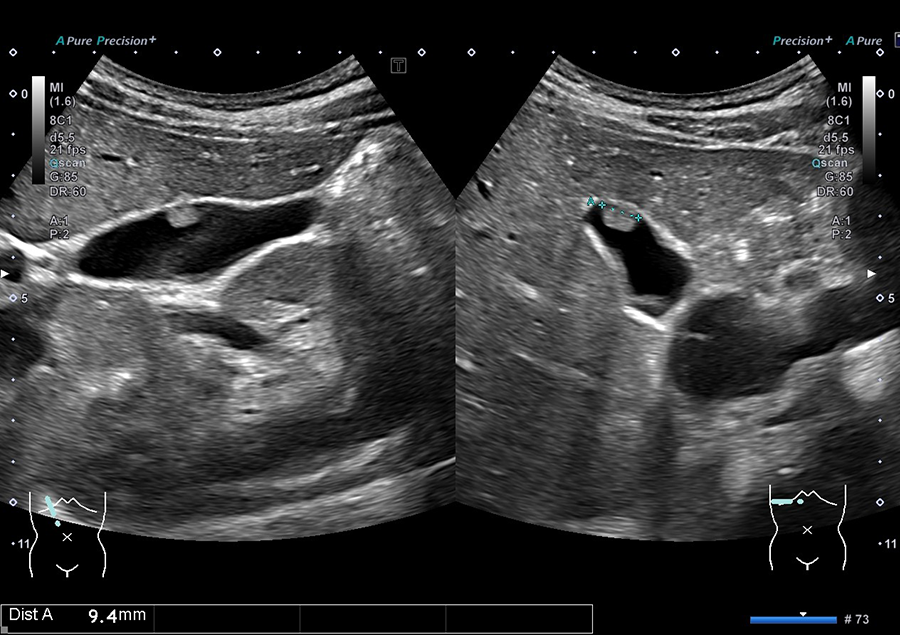

02.最新の超音波診断装置を導入

当院では、キヤノンメディカルシステムズ株式会社の超音波診断装置「Aplio a Verifia」を導入しています。

- ノイズを低減し、クリアな画質で病変を検出

- 従来の腹部エコーに比べ、広範囲を一度に撮影可能で、病変の位置がより分かりやすく確認できます

- 送信・受信技術(Advanced Sync Pulser と Advanced Beam Receiver とMulti-Harmonic Compounding)により、高精細な画像を提供

- 低流速血流の観察に適したSMI で、病変を詳細に観察

高精細な画像と優れた解析技術により、正確に観察することが可能です。